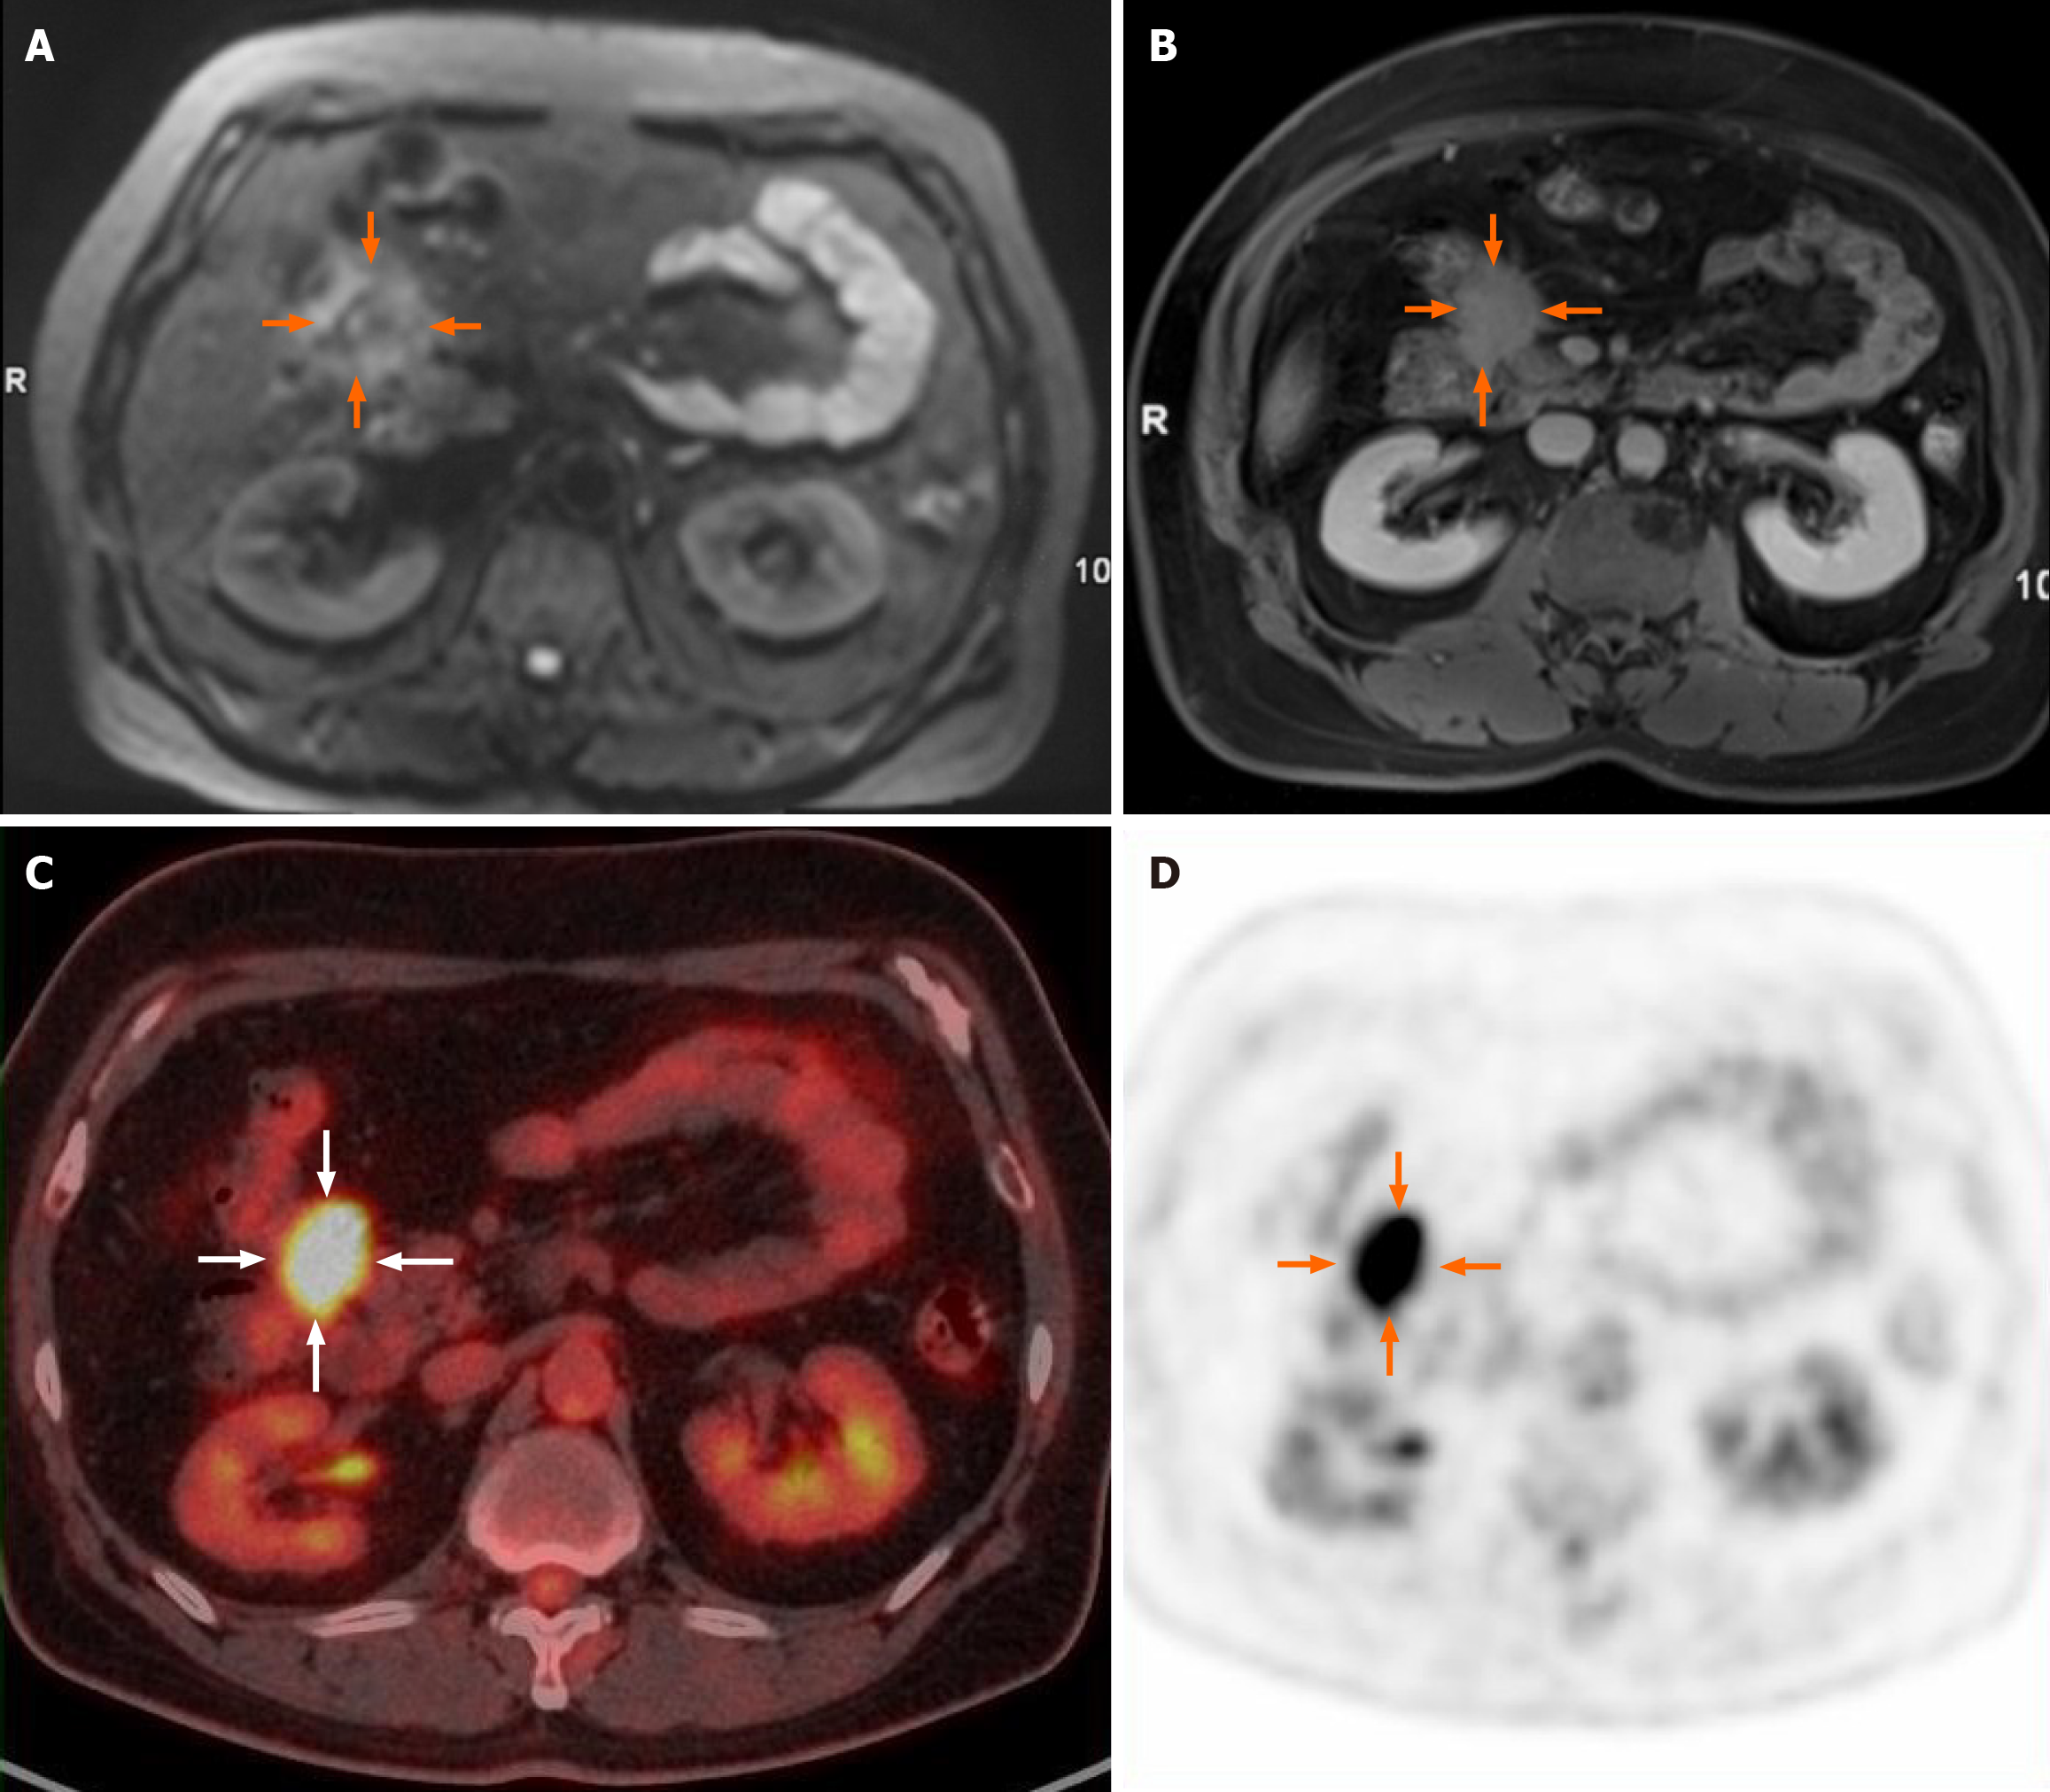

Abdominal magnetic resonance imaging (MRI) revealed an irregular soft tissue mass exhibiting slightly high signal intensity on both T1-weighted and T2-weighted images. The tumor displayed infiltrative changes with poorly defined margins and extended into adjacent structures, including the head of the pancreas and the hepatic flexure of the colon. Notably, it encircled the anterior superior pancreaticoduodenal artery. On diffusion-weighted imaging (DWI) with a β value of 800 mm²/second, the lesion showed slightly to moderately high signal intensity (Figure 1A), with the corresponding apparent diffusion coefficient (ADC) average value of 1.27 × 10-3 mm²/second for the maximum slice. Dynamic contrast-enhanced images indicated uneven enhancement during the arterial phase, with significant enhancement observed in the delayed phase (Figure 1B). 18F-fluorodeoxyglucose (FDG) positron emission tomography (PET) revealed increased uptake in the tumor (Figure 1C and D), with a maximum standardized uptake value (SUVmax) of 10.3. No abnormal lymph nodes were detected on PET/computed tomography (CT) images. Given the infiltrative characteristics of the tumor, a malignant neoplasm was suspected.